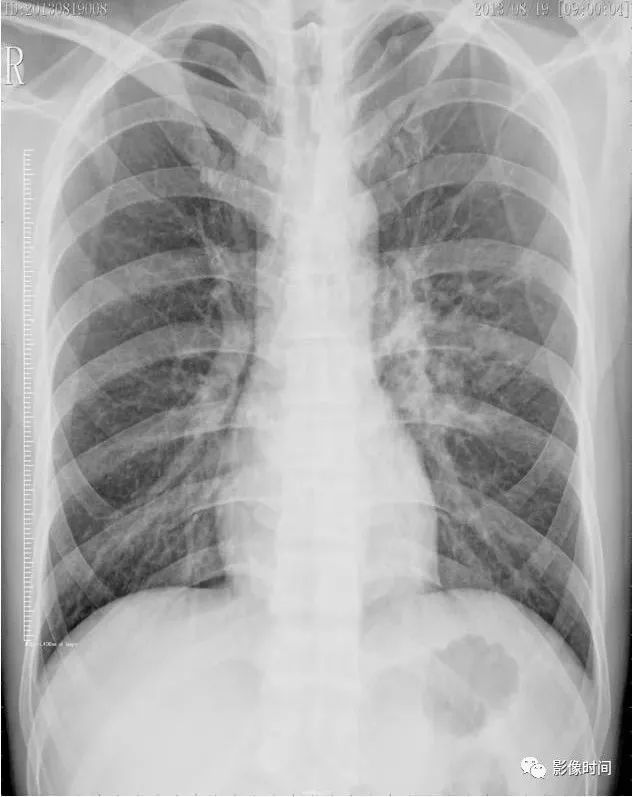

胸片可见两肺弥漫炎性渗出影,因此诊断为小儿支气管肺炎